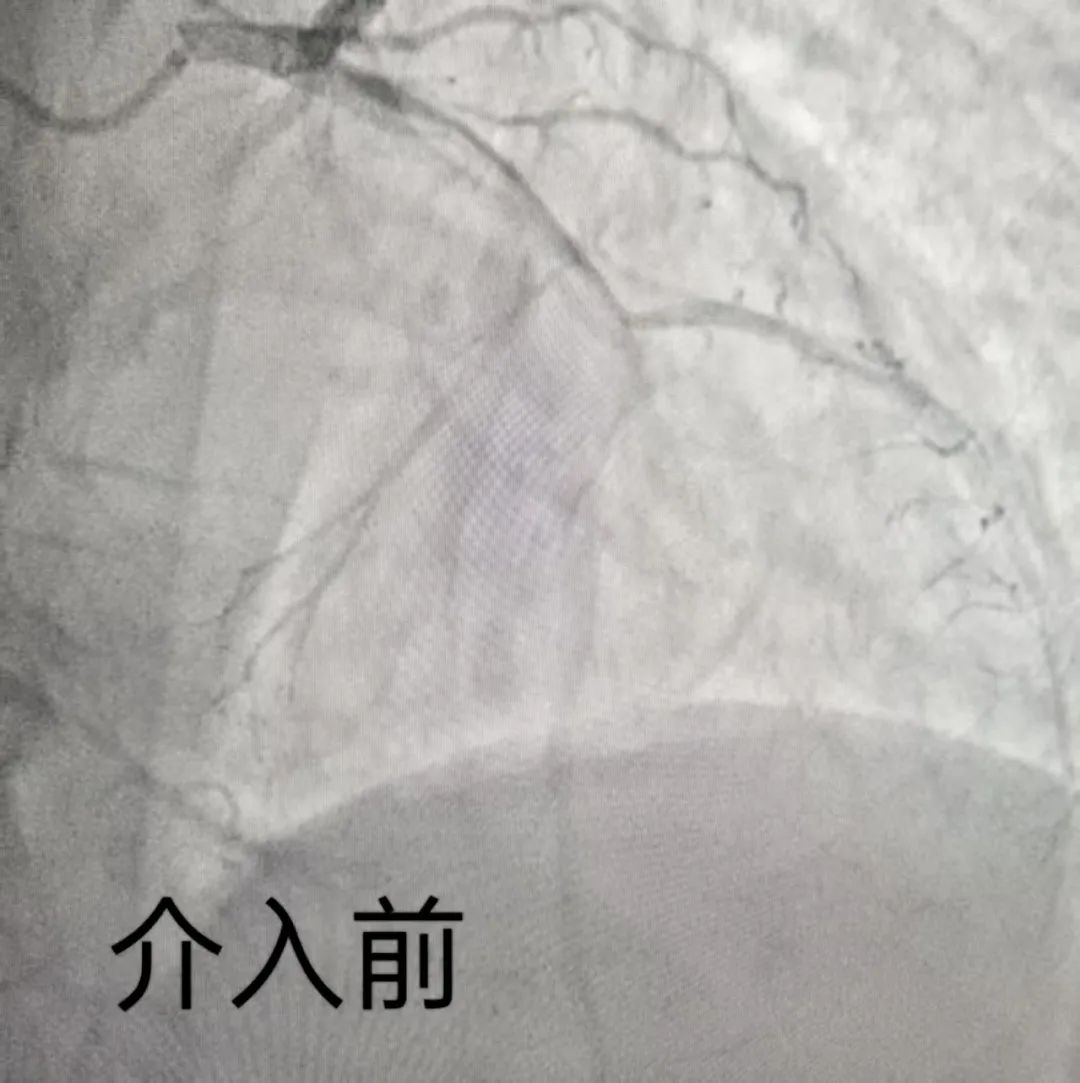

冠脉造影检查揭示的病情比预想更为凶险:三支心脏供血的大血管均存在严重狭窄病变,而此次引发致命心梗的罪犯血管正是至关重要的左前降支。于主任手术团队精准施治,迅速在左前降支成功植入两枚支架,患者症状得以迅速缓解。

从社区确诊到支架植入开通血管,全程仅用59分钟,生动诠释了“时间就是心肌,时间就是生命”。社区初筛识别、高效绿色通道转运、导管室无缝衔接,每一环都在为跑赢死神而冲刺,最终保证了患者的生命安全。